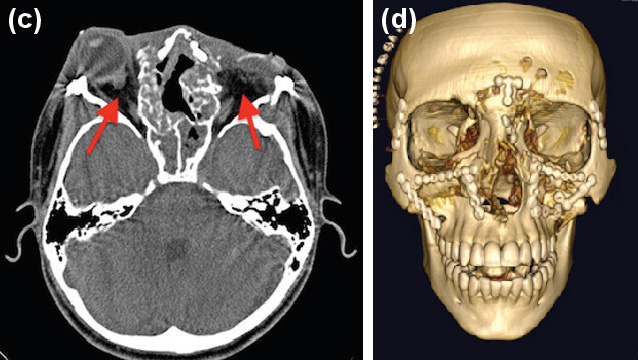

事故で両目が飛び出てしまった男性の手術前と後の画像。